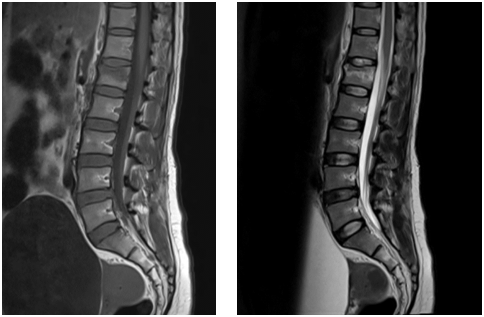

Tại Khoa Ngoại Chấn Thương, bệnh nhân được chụp CLVT, MRI cột sống ngực lưng, kết quả: Vỡ xẹp thân đốt sống L1 và có phù mô xương xốp. Êkip bác sĩ Ngoại CTCH và DSA tiến hành hội chẩn và tư vấn gia đình hướng điều trị bằng phương pháp bơm xi măng sinh học.

Hình chụp MRI cột sống thấy xẹp đốt sống L1 có phù mô xương xốp